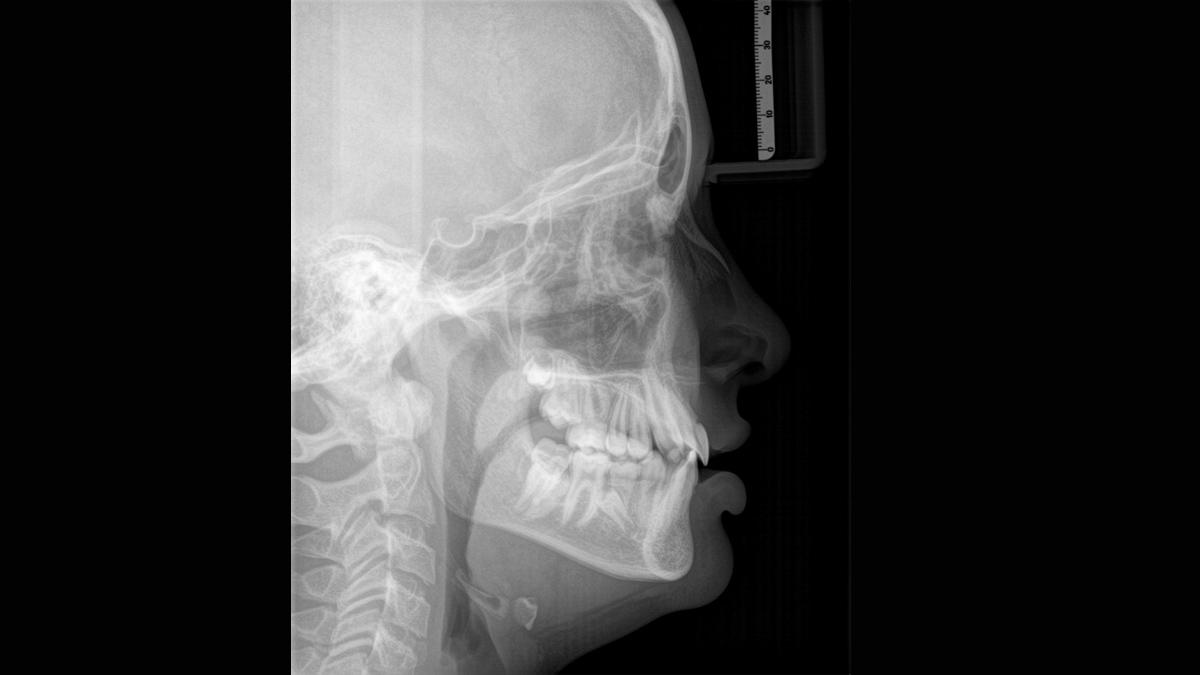

Wij hebben een 10-punts concept ontwikkeld voor eenvoudige positionering van de patiënt en röntgenbeeldvorming. Ons concept draait in de eerste plaats om twee dingen: hoge beeldkwaliteit en comfort voor de patiënt en de assistent. Dit concept ondersteunt en biedt de hulpmiddelen die nodig zijn om beelden van hoge kwaliteit te garanderen voor de analyse van de behandeling en richt zich op ergonomie en comfort voor de patiënt en de assistent. De gepatenteerde bijtblok technologie, bijvoorbeeld, stelt automatisch de juiste helling van het hoofd van de patiënt vast, positioneert de patiënt in het occlusale vlak, werkt samen met de 3-punts hoofdfixatie en stevige handgrepen om een stabiele positionering te garanderen, waardoor onnodige correctiescans worden beperkt.